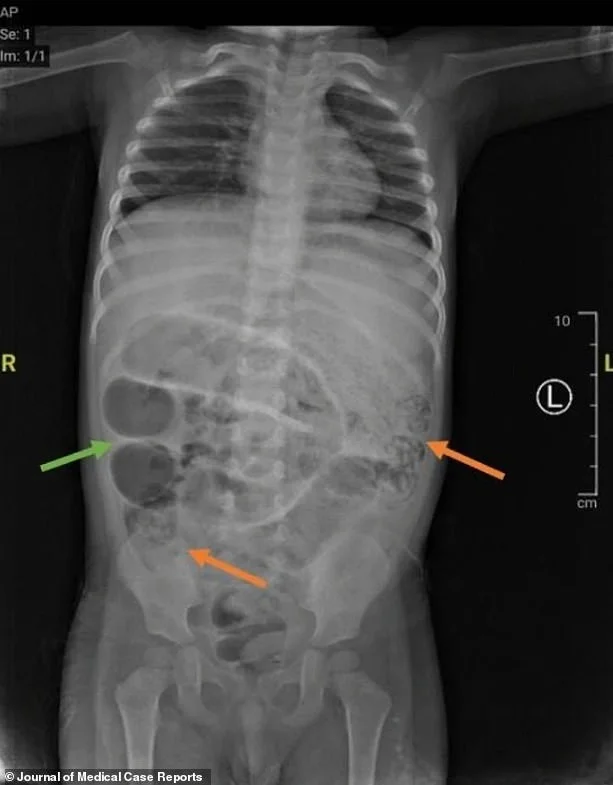

У маленького пациента начались рвотные позывы, в которых обнаружились черви, а рентгенологическое исследование желудка выявило серые образования, указывающие на «кишечную непроходимость».

Хирургическая команда выполнила лапаротомию — разрез брюшной полости — и нашла червей, блокирующих три участка тонкой кишки. Паразиты были извлечены и направлены в лабораторию для дальнейшего анализа.